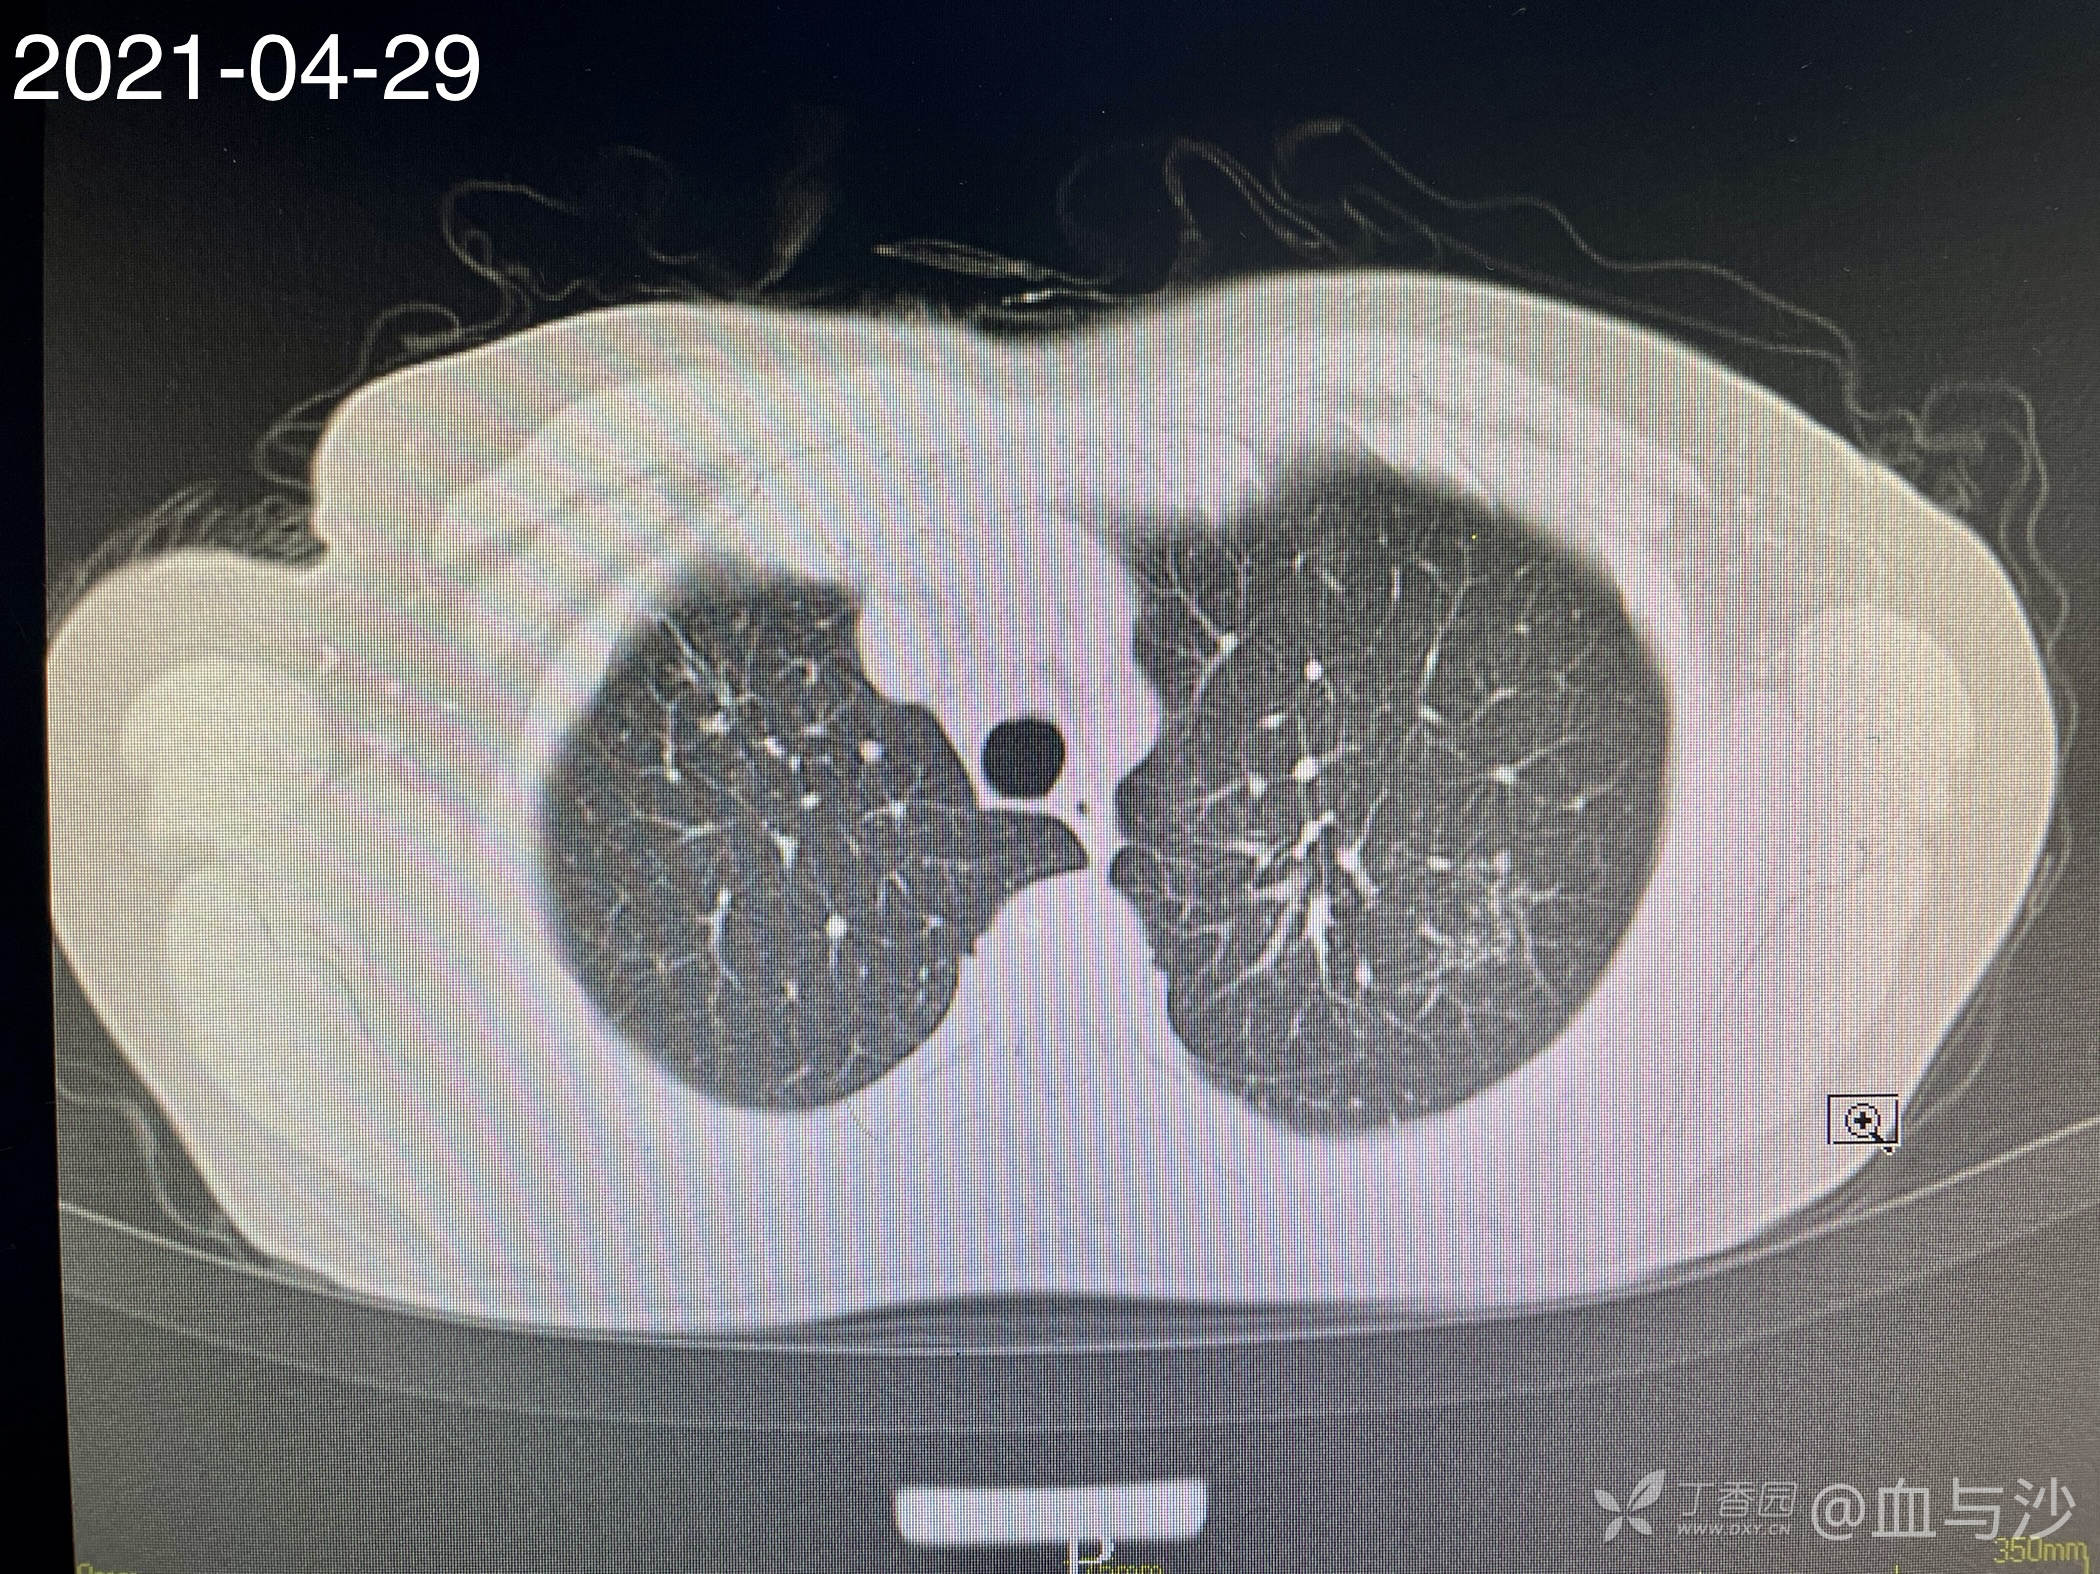

病人女,60岁,去年4月底因咳嗽发热入院,诊断支气管扩张伴感染(结核各项检查阴性,病人平时也无潮热盗汗),予抗感染对症处理。当时CT片左肺上叶有一磨玻璃样影。今年5月病人再次咳嗽发热入院,续按照支扩伴感染处理,但CT显示去年的磨玻璃影成了一约1.5cm的实性结节。